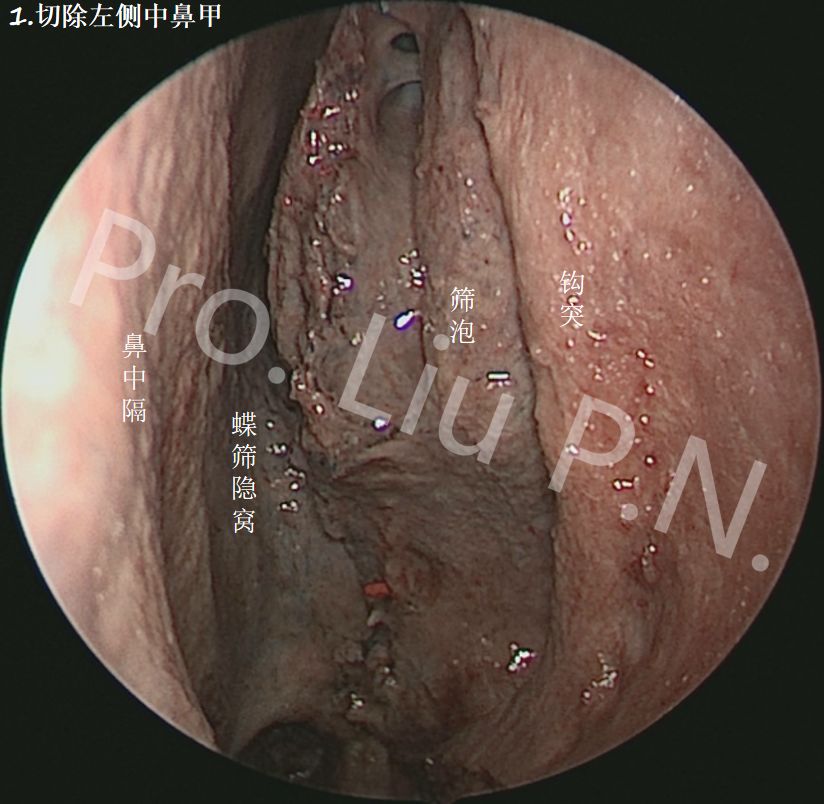

1. 切除左侧中鼻甲

2. 切除部分前后筛房

3. 切除后筛,显露蝶窦前壁及翼腭窝前壁

4. 去除蝶窦侧壁及翼腭窝表面骨质

九、经筛-翼突入路显露海绵窦范围

经筛-翼突-海绵窦入路是对蝶窦侧壁、海绵窦区域暴露最好的手术方式,尤其是切除V2神经鞘瘤及翼管神经鞘瘤,有天然的解剖合理性,切除中鼻甲下部有助于海绵窦中下三分之一的暴露。